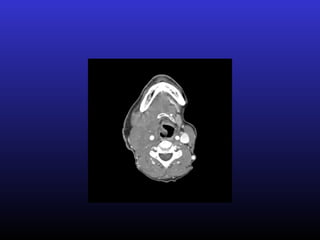

• #10 patient with H&N cancer – large R sided mass – ex. Somatic pain